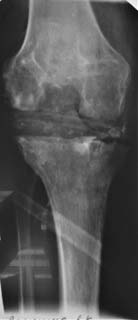

Уважаемые коллеги! Пациент мужчина 62 года, эндопротезирование коленного сустава в сентябре 2011 в одном из соседних учреждений. Множественные операции по восстановлению связок в анамнезе. Под наше наблюдение попал спустя 3 месяца с клиникой глубокой перипротезной инфекции. Гнойный свищ, MRSA в посеве. Выполнено удаление протеза, некрэктомия, установка цементного спейсера. Заживление первичное, а\б терапия по посевам, в течении 2 месяцев положительная динамика, нормализация лабораторных показателей. В последующем усиление болей, отек, разрушение спейсера по рентегнограммам. Взят в операционную для повторной некрэктомии, удаления спейсера. Во время операции выявлено- отсутствие явного гнойного содержимого, ткани более жизнеспособные, чем во время первого удаления, отсутствие значительного прогрессирования костных дефектов. Решено от одномоментного артродеза воздержаться, конечность стабилизирована дистракционным аппаратом. В интраоперациооных посевах St.aureus. В настоящее время две недели после операции, встает вопрос о возможностях далнейшего лечения. Ревизонное колено? Еще раз после спейсера или сразу? Или артродез?